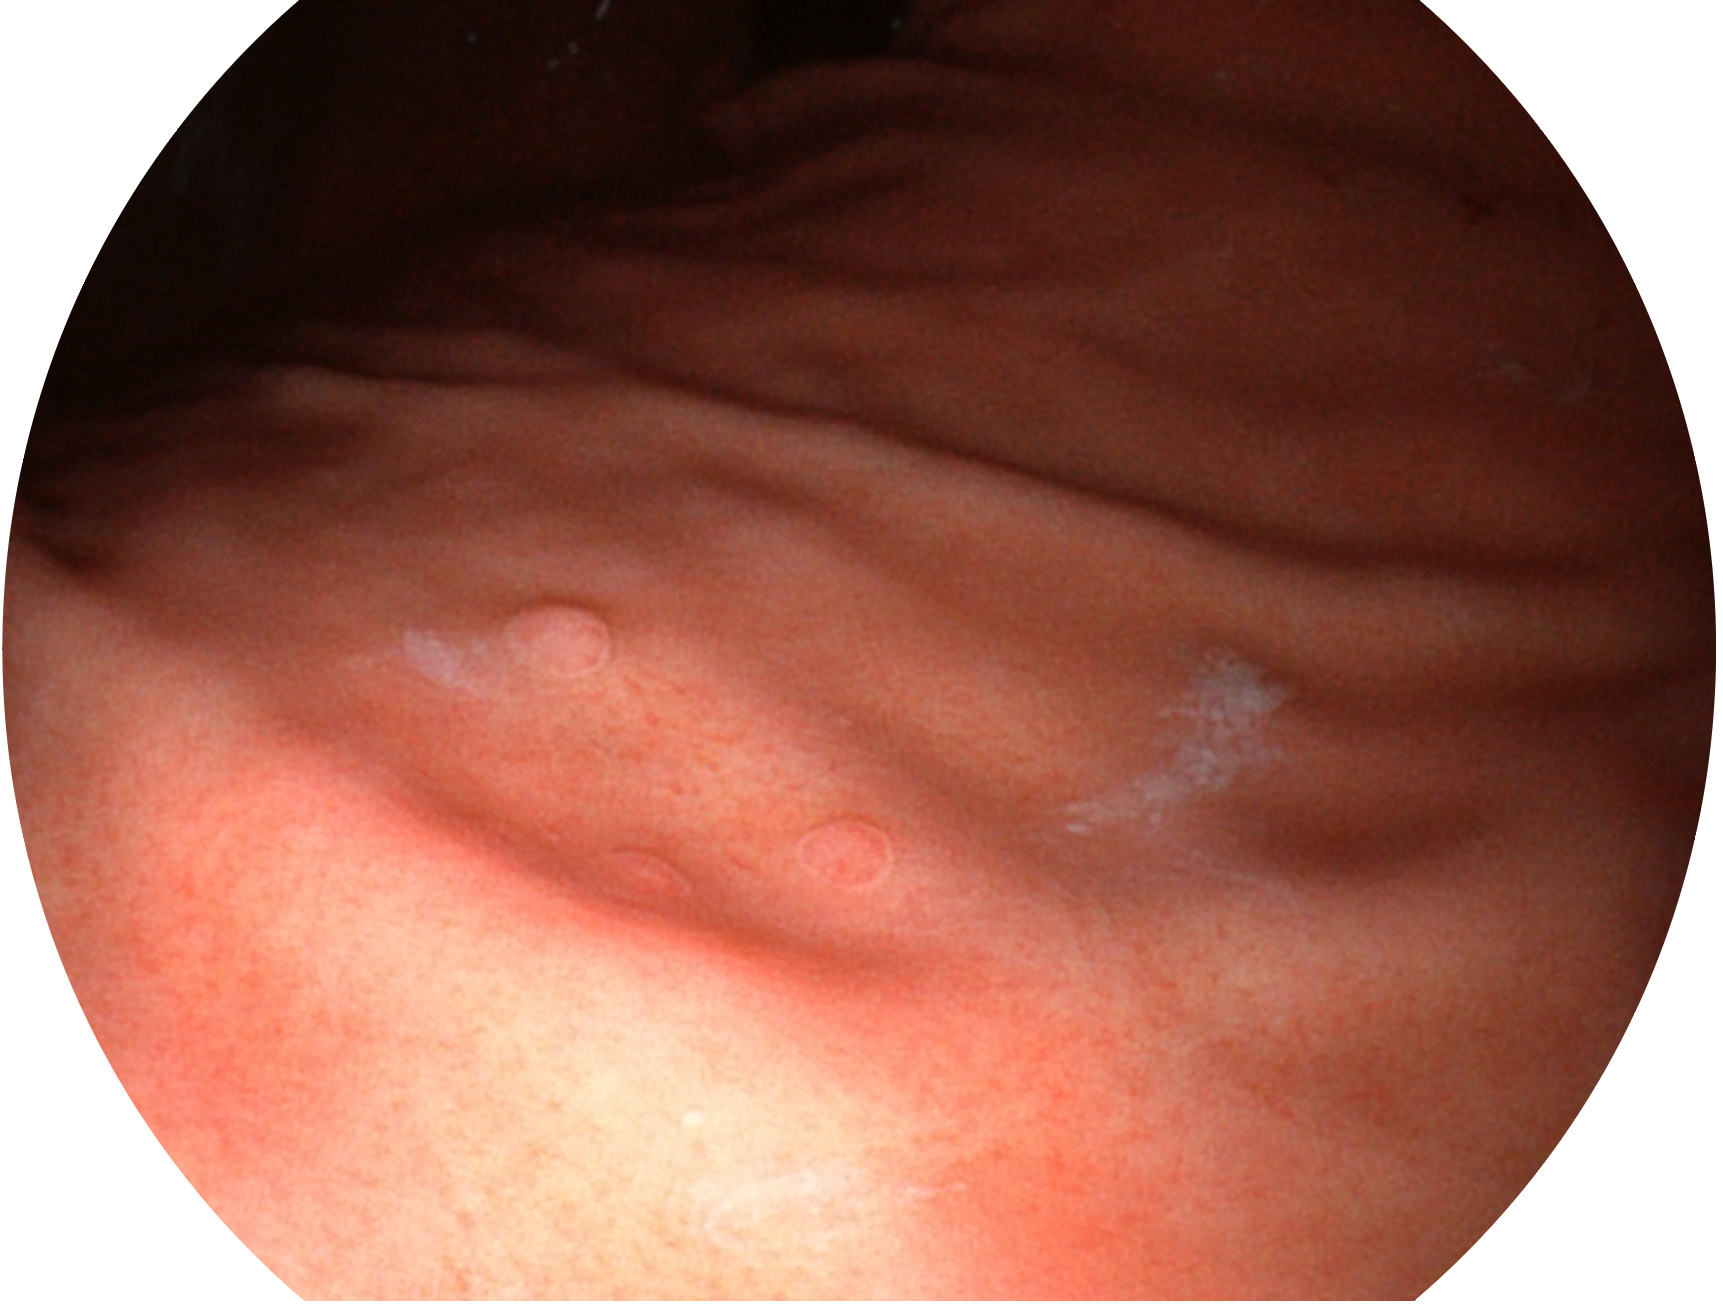

诸侯快讯官网新开发的内镜染色技术,主要是基于多波长LED 光源的开发,VLS-55Q 四波长LED 光源是由四个不同颜色的LED光按照相应照明模式所规定的特定发光比例进行合束后形成,合束后形成的照明光的光谱由红光、绿光、蓝光及蓝紫光这四个不同的波段范围构成。具有更高光谱自由度,通过光谱比例的控制,实现了聚谱成像技术,英文全称为“Spectral Focused Imaging, SFI”,缩写为“SFI”和光电复合染色成像技术,英文全称为“Versatile Intelligent Staining Technology, VIST”,缩写为“VIST”。